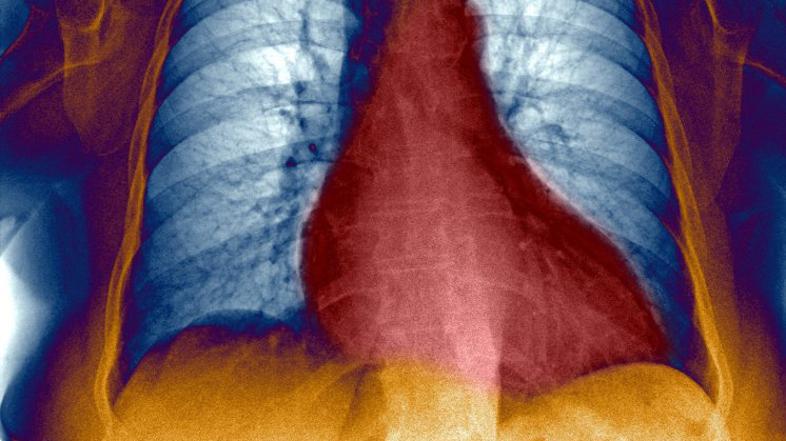

Razširjeno srce